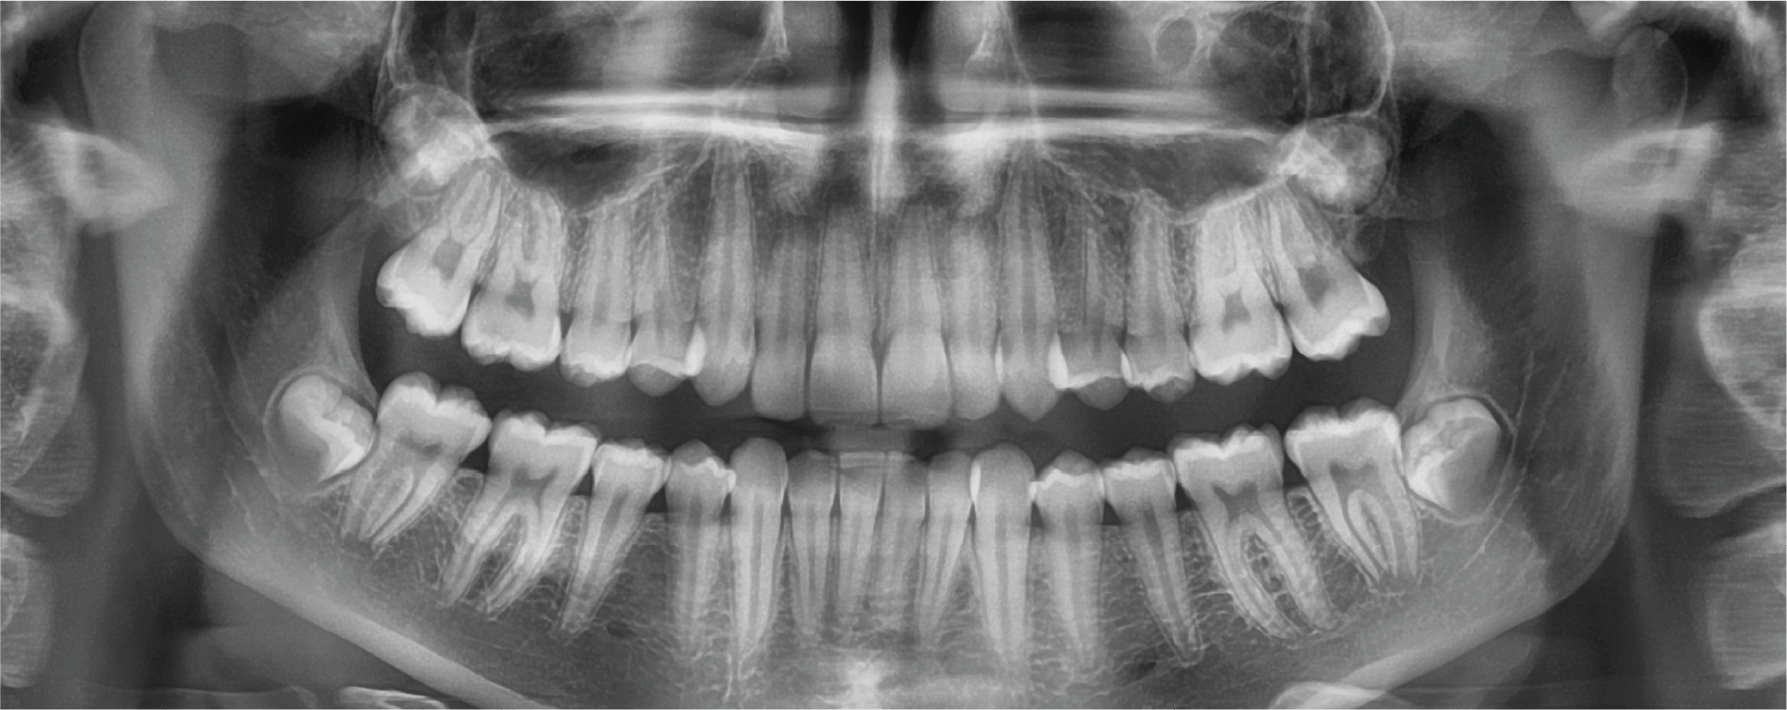

SUPERIOR IMAGE QUALITY

– Optimal image for accurate diagnosis

THE ADVANCED IMAGING SOLUTION FOR ACCURATE DENTAL DIAGNOSIS

The Pax-i OPG provides the most precise and high quality panoramic images by combining image processing and accumulated experience in dental imaging from Vatech. This will increase your diagnostic accuracy for improved treatment planning and patient satisfaction.

THE ADVANCED IMAGING SOLUTION FOR ACCURATE DENTAL DIAGNOSIS

The Pax-i OPG provides the most precise and high quality panoramic images by combining image processing and accumulated experience in dental imaging from Vatech. This will increase your diagnostic accuracy for improved treatment planning and patient satisfaction.

MAKE YOUR DIAGNOSIS EASY AND EFFICIENT WITH VARIOUS CAPTURE MODES

MAKE YOUR DIAGNOSIS EASY AND EFFICIENT WITH VARIOUS CAPTURE MODES